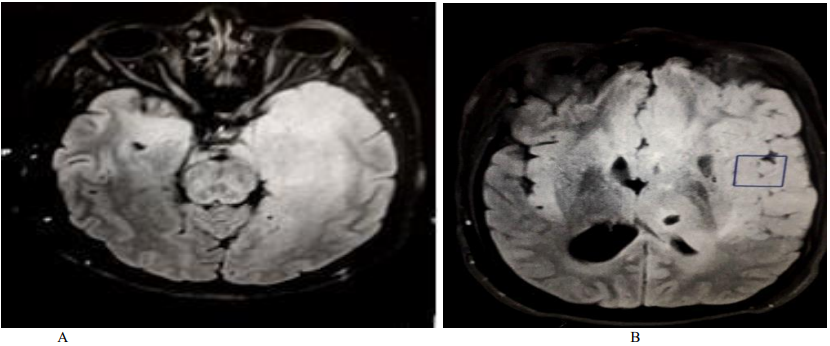

The patient received Methylprednisolone IV (1g / day for 5 days) with an oral relay (1mg / kg / day), combined with anti-epileptics (Levetiracetam 3g / day, Lamotrigine 200mg / day). The evolution was marked by a persistence of the epilepsy attacks, an appearance of headache and oculomotor disorders (diplopia, left exophthalmia), and see obnubilation. Control MRI showed an aggravation of the lesions with mass effect and bilateralization of the hyper signal (Figure. 3). The brain biopsy was done urgently and returned in favor of a gliomatosis (oligodendrogliale). The child was treated with radiotherapy, with disappearance of disturbances of consciousness and seizures, and persistence of hemiparesis.

Figure 3. Control brain MRI (FLAIR sequences, cross section): extensive hyper signal affecting the fronto-temporo insular white matter, bilaterally, with mass effect.